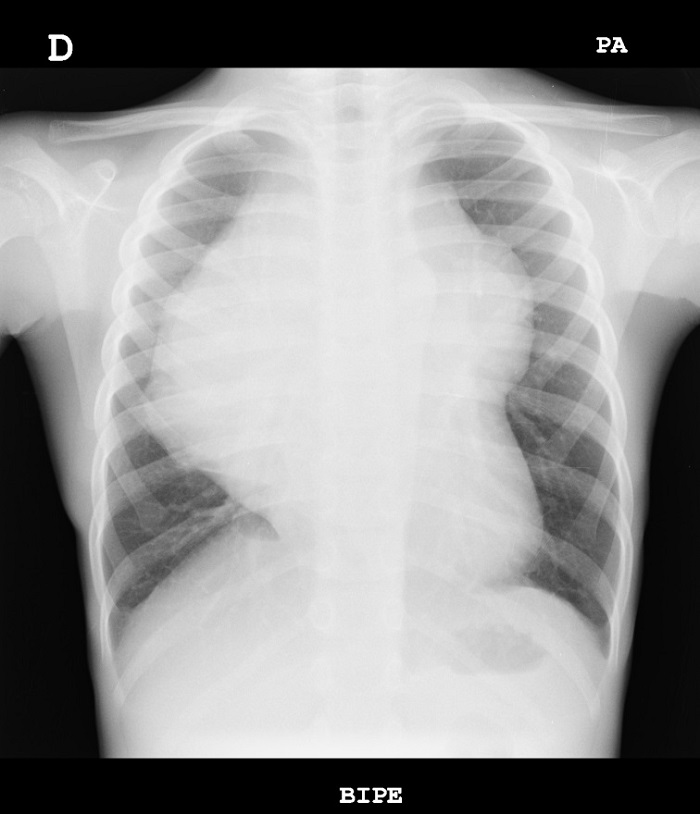

En la radiografía se observa una masa mediastínica que deja ver a su través los vasos de los hilios pulmonares, por lo que probablemente se localiza en mediastino anterior.

No presenta afectación de campos pulmonares, pleura o estructuras óseas.